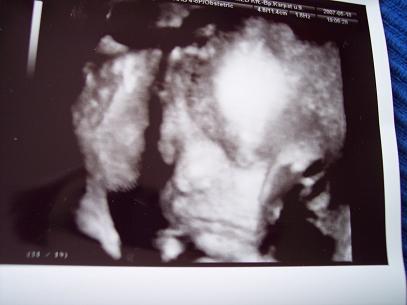

Jucu és a "hasa" :-)

íme a "has" :-) 26 hetes picurunk